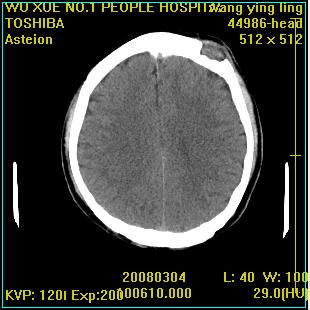

标题: CT12023:女,50岁,头部包块二月,伴轻微头痛,不伴发热。 [打印本页]

标题: CT12023:女,50岁,头部包块二月,伴轻微头痛,不伴发热。

这种病例还是比较多见,起源于颅骨板障,向颅内和颅外生长,考虑血管瘤或嗜酸性肉芽肿,要是有增强ct就好了。

多发溶骨性破坏,骨嗜酸性肉芽肿可能,转移瘤待排除,建议进一步检查。

破坏区边界较清楚,还是考虑良性病变---嗜酸性肉芽肿可能。

颅骨多处破坏伴软组织肿块,考虑为转移瘤可能性大。

病灶呈溶骨性骨破坏,考虑嗜酸性肉芽肿可能转移瘤不除外建议追查病史并进一步检查